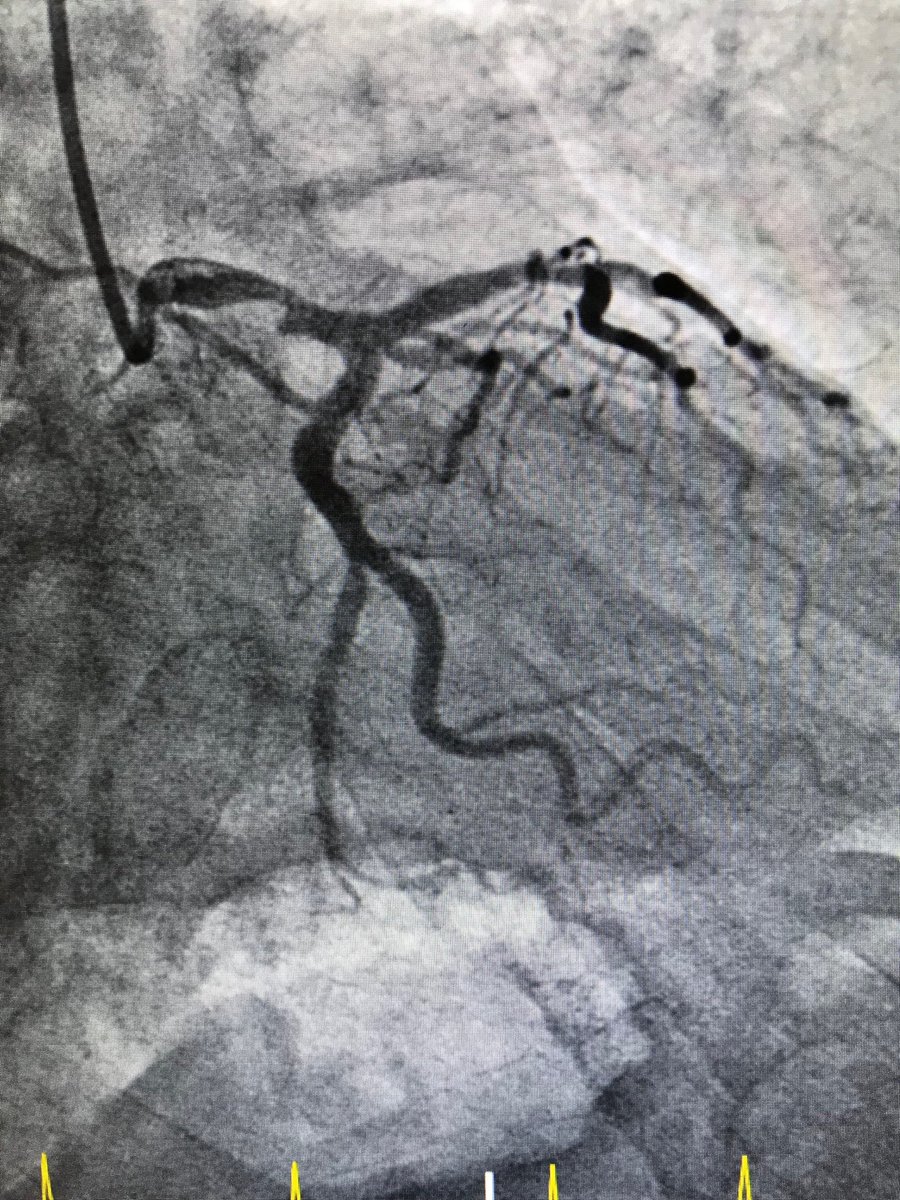

#protectedpci #RadialFirst #impella #safefemoral#ivus##unprotectedleftmainpci 61f#nstemi.6f45pinnacle inside 14f sheath .Successful #LMpci .left cfa occluded. bailout 014”grand slam/8x2balloon via rt radial. failed preclose ,safe balloon hemostasis while act240sec.#NoHematoma

istentem's tweet image. #protectedpci #RadialFirst #impella #safefemoral#ivus##unprotectedleftmainpci 61f#nstemi.6f45pinnacle inside 14f sheath .Successful #LMpci .left cfa occluded. bailout 014”grand slam/8x2balloon via rt radial. failed preclose ,safe balloon hemostasis while act240sec.#NoHematoma